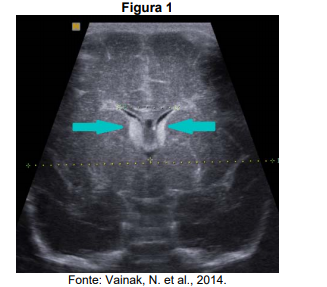

Considere a imagem ultrassonográfica apresentada na figura 1, que representa um exame transfontanela de um recém-nascido pré-termo, parto vaginal, com alterações no quadro respiratório.

O plano anatômico da imagem ultrassonográfica e a hipótese diagnóstica mais provável, correspondem, respectivamente, a